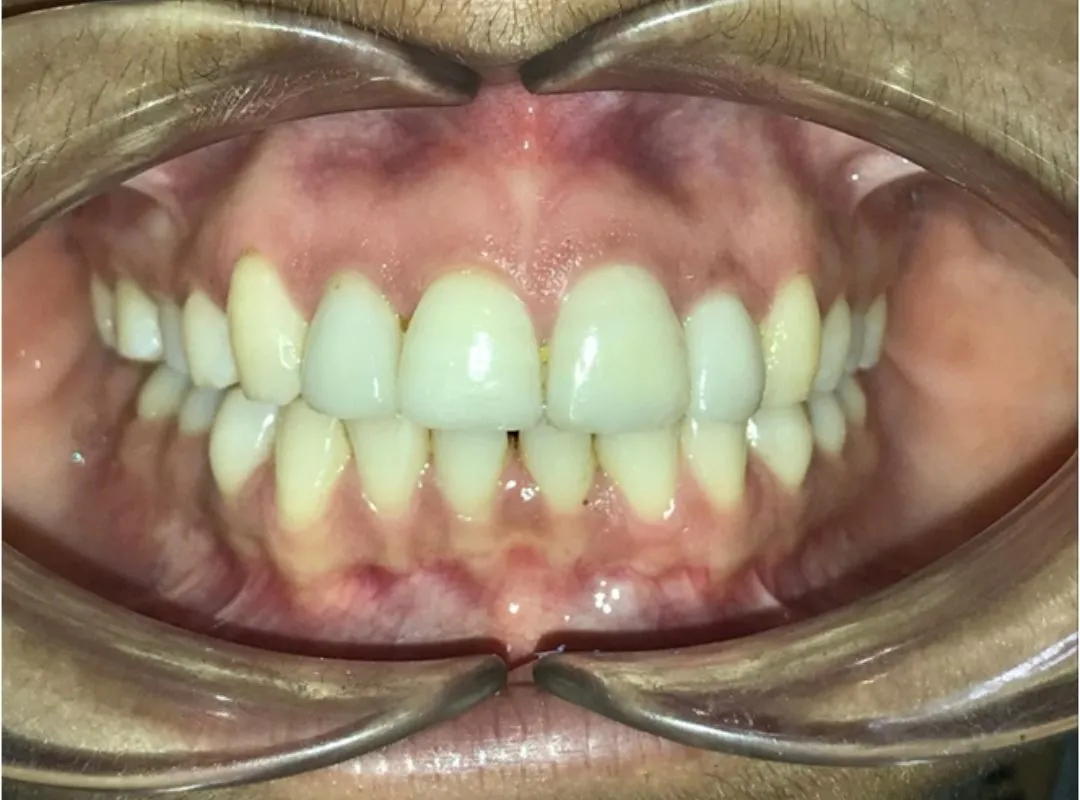

I had undergone my teeth Aligner process at JP dental, Perambur,which was over a period of 8 months. Journey was of 12 levels of aligners and after each level my teeth were thoroughly evaluated to ensure the process was smooth and progressive. The doctors here are very professional and have upto date equipments which gave me a very great outcome from my journey here. Highly recommend .create a caption for this review